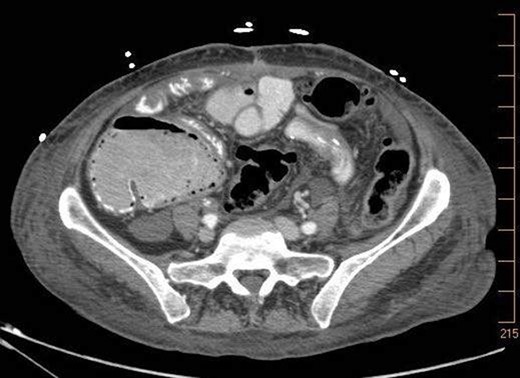

On 7.8.18 the patient had return of bowel function complicated by blood per rectum and an episode of bloody emesis with drop in Hgb 9 > 7.0. The patient received 2 units PRBCs. GI consulted deemed blood per rectum likely from bleeding from anastomoses line. 7.8 Zosyn began for 7 days. Due to the concern for potential bleed, on 7.9 the patient had CTAP (Fig. 5) which demonstrated newly developed pneumatosis within ascending and transverse colon. Pt at this time had appropriate post-surgical abdominal pain, no leukocytosis 4.6, and was HDS. Decision was made to conservatively manage this form of colonic pneumatosis, with TPN, antibiotics, and bowel rest. 7.11 EGD revealed a 5 mm ulcer at duodenal bulb. CTAP (Fig. 6) on 7.14.18 demonstrated largely resolved pneumatosis of ascending and transverse colon. 7.17 Mechanical soft diet, discharged home.

7.14.18: CTAP w/IV and PO contrast: largely resolved pneumatosis.